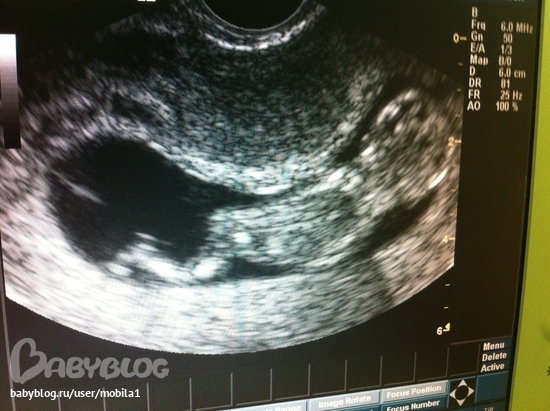

Сегодня ходила с мужем на узи. Это было здорово!!!! Он ворочался во все стороны, махал ручками и ножками. Мы не думали что они такие активные на таком маленьком сроке - 12 нед и 3 дня : ))))) Есть вероятность что будет мальчик, надеюсь так и будет!

Сердцебиение - 150 уд.

КТР - 58 мм

Диаметр желточного мешочка - 7 мм

БПР - 19 мм

ЛЗ - 23 мм

ТВП - 1,1 мм

ДБ - 7 мм

Если кто-то знает объясните что означает весь этот шифр? Знаю только что значит КТР.

БПР это бипариетальный размер головы, ТВП это толщина воротникового пространства, ДБ это длина бедренной кости. Что такое ЛЗ не знаю, все перекопала и не нашла. Все показатели у вас в норме!!! ПОЗДРАВЛЯЮ!!!!!!!!!!!!

Да здорово))) в 12 недель мне малышка ручкой махала )) папа проникся? Параметры я тебе попрбую завтра расшифровать! ))) милаха на фото)))